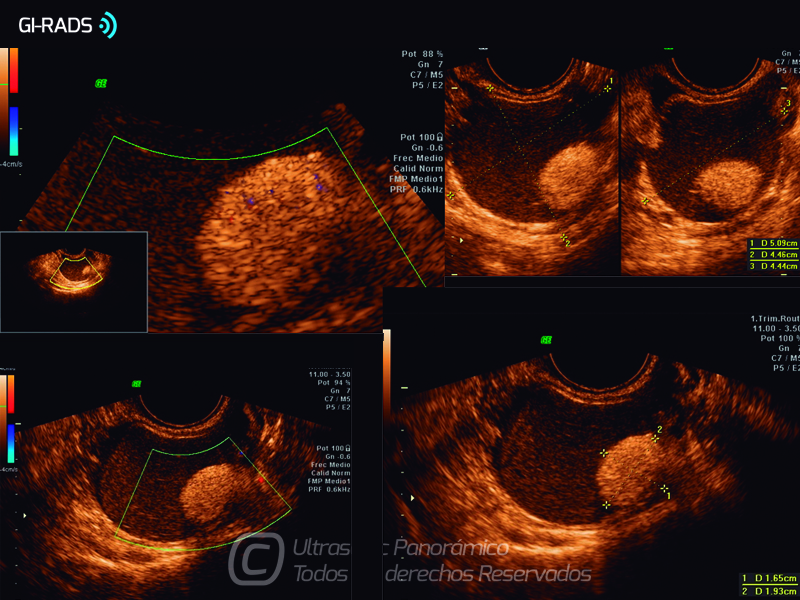

Patologías Benignas – Teratoma Maduro

• Patologías Benignas – Teratoma Maduro